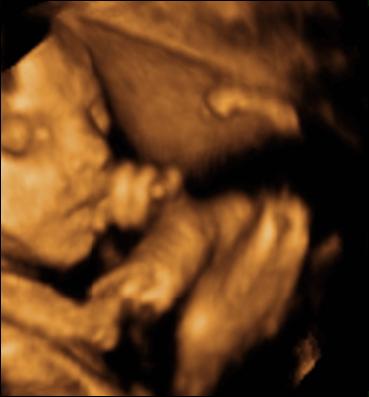

A második képen nyitva van a szeme is